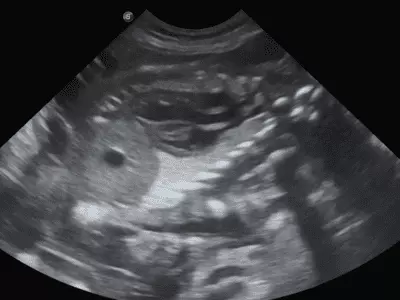

W tym wydaniu m.in: problemy trawienne, dermatozy psychogenne psów, przepuklina brzuszna pępkowa zewnętrzna, szpiczak mnogi, starszy pies z objawami krwioplucia, przegląd objawów behawioralnych w kontekście różnych chorób.